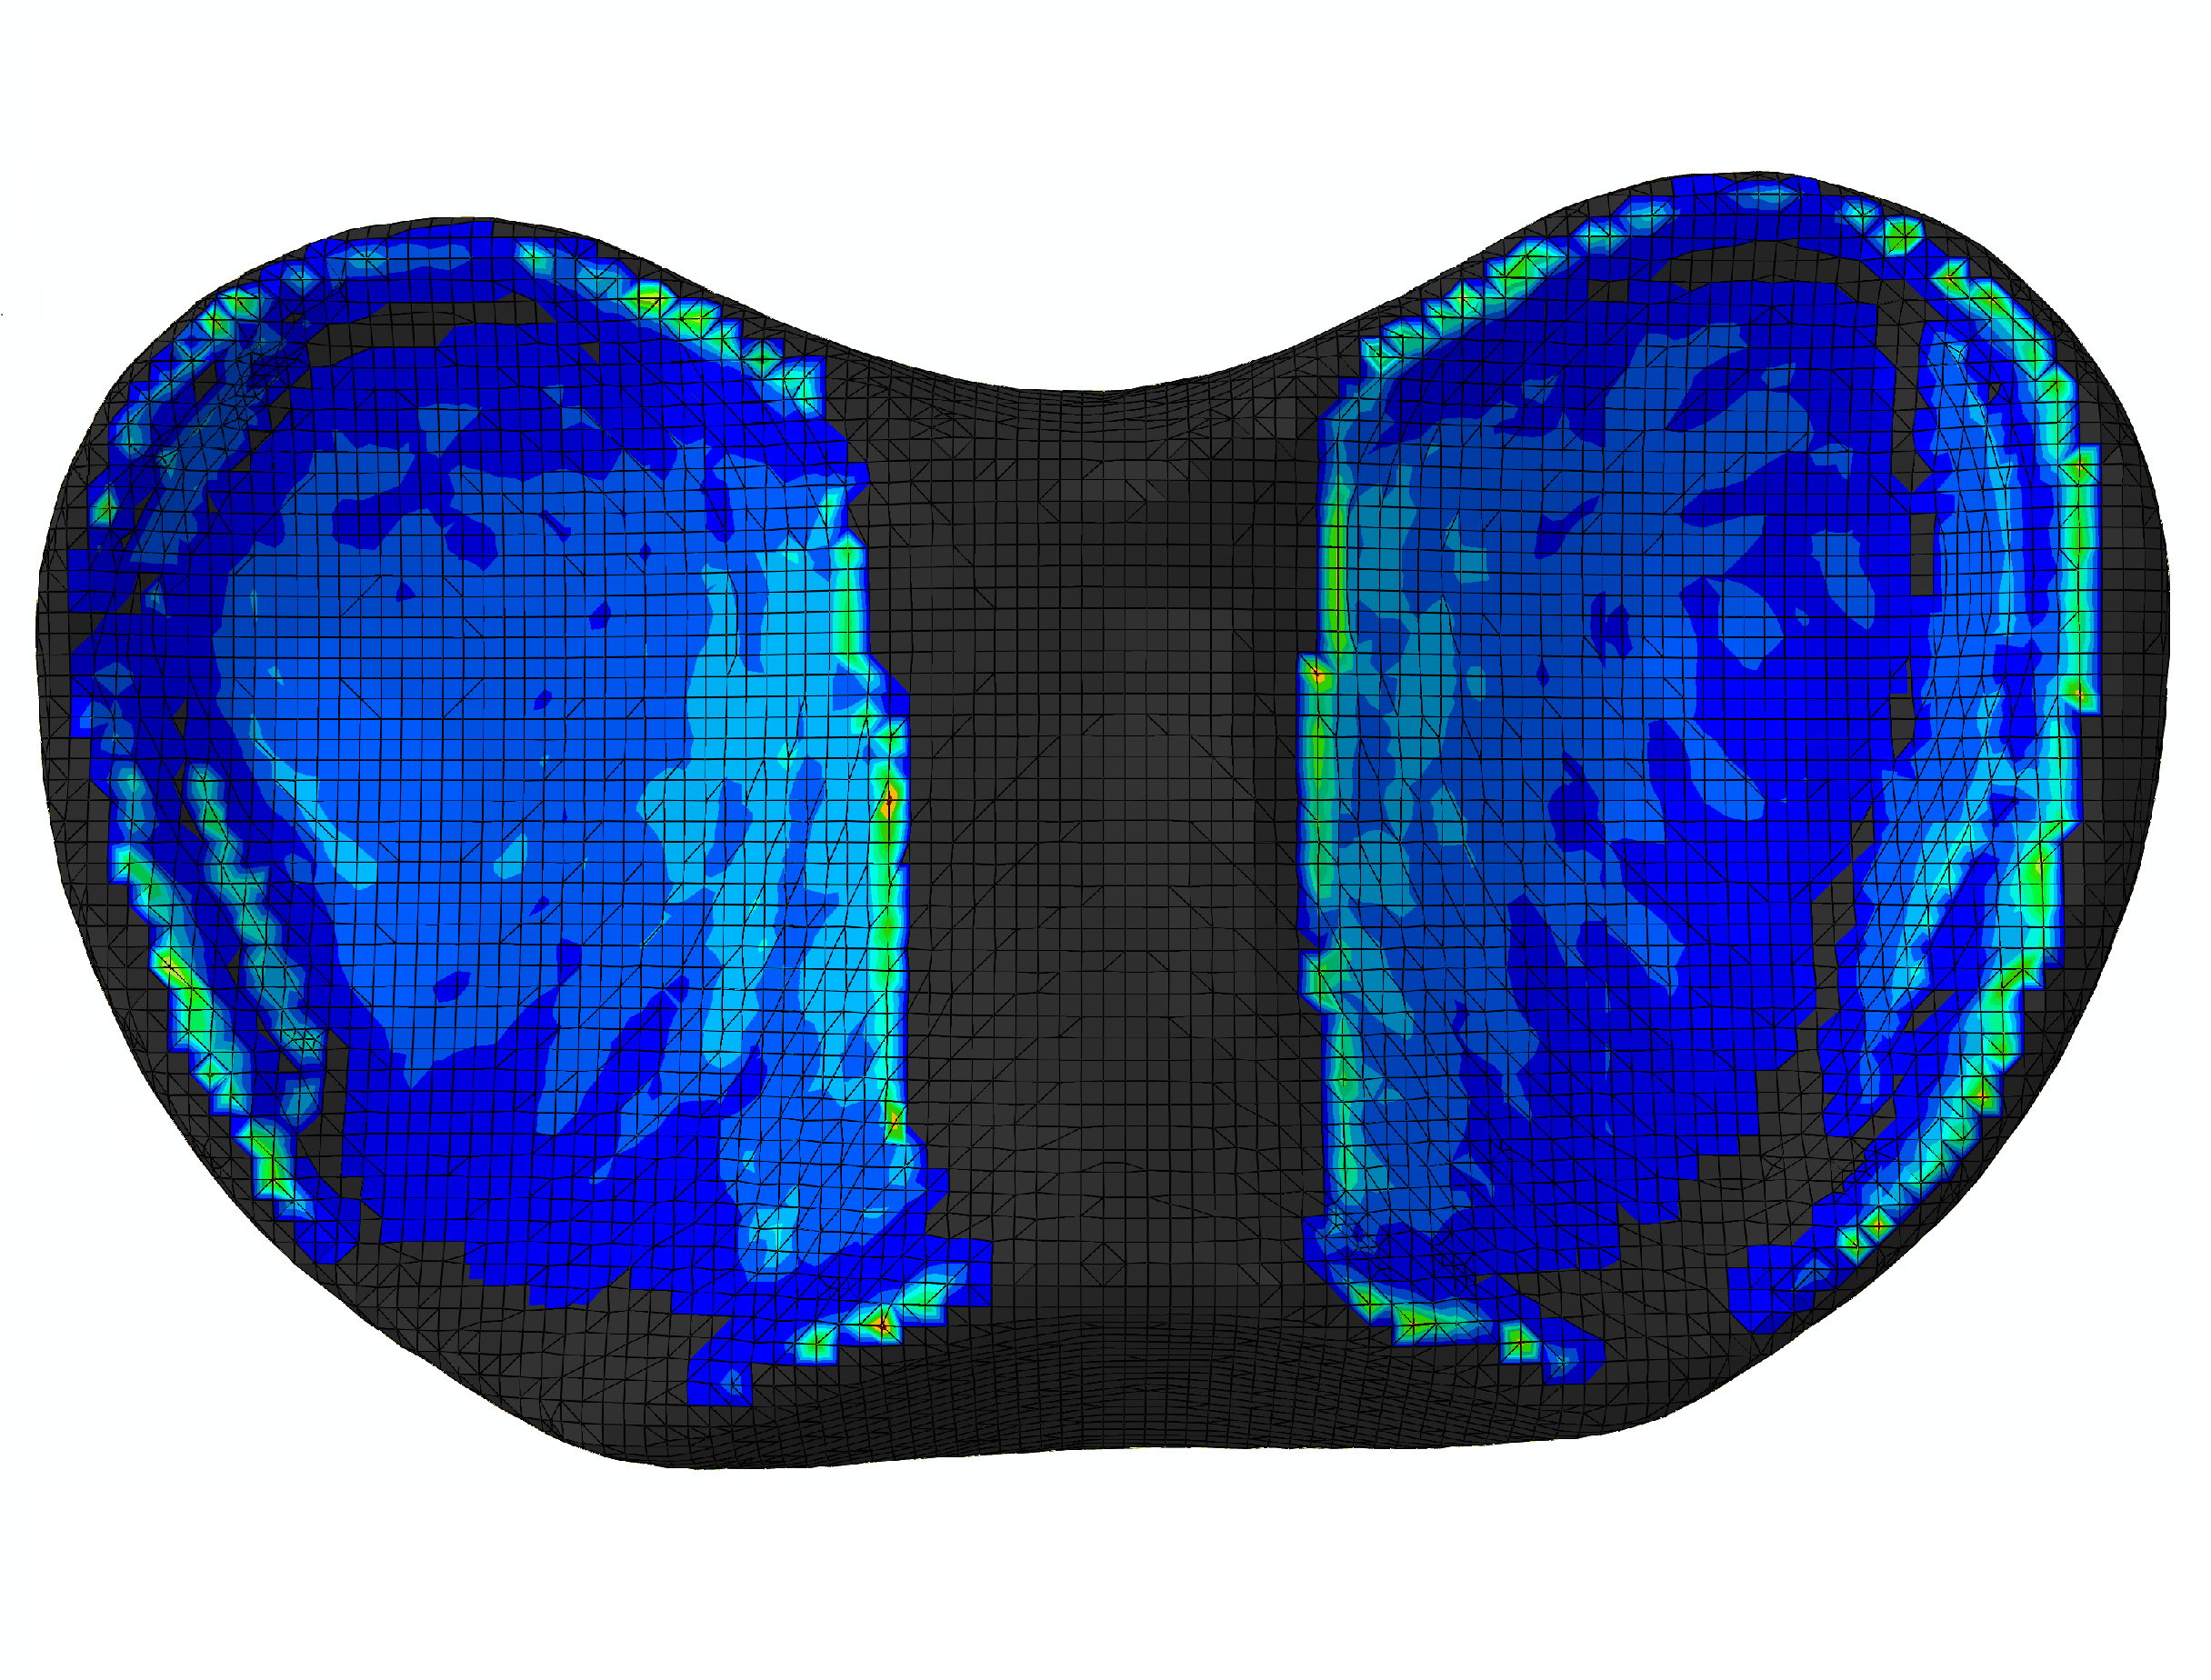

The bottom surface of the tibia head is fixed, and two translational DOFs in the horizontal plane of the top surface of the femur head are also constrained. On the top surface of the femur head, a vertical load of up to [72] is applied to induce contact in the knee joint. The displacement contours () from different views are shown in Fig. 32. It is obvious that the deformation occurs mainly in the meniscus. The femur, tibia and articular cartilages are similar to rigid bodies. This phenomenon meets the expectation because the Young’s modulus of the meniscus is significantly smaller than those of the bones and articular cartilages. The meniscus is squeezed into the joint space and there is lateral extension of the meniscus. The large deformation of the meniscus increases the contact area which is helpful to reduce the contact pressure.

The contact pressure distributions () are depicted in Fig. 33. To illustrate the distribution clearly, contact pressure values smaller than are not included in the contour. It is obvious that the contact pressure on the articular cartilage has a similar distribution and magnitude compared to that on the meniscus. Besides, the contact pressure on the articular cartilage has a similar distribution from Ref. [72].

The development of the contact on the articular cartilage is recorded, as depicted in Fig. 34. Note that only the area where the contact pressure is greater than has been taken into account. Generally speaking, with increasing the vertical load , the contact area is increasing while its increasing rate is reducing. The average contact pressure increases during the loading history. Before the vertical load increases up to , the increasing rate of the average contact pressure is basically reducing. However, when the average contact pressure increases almost linearly because the contact area increases only slightly.